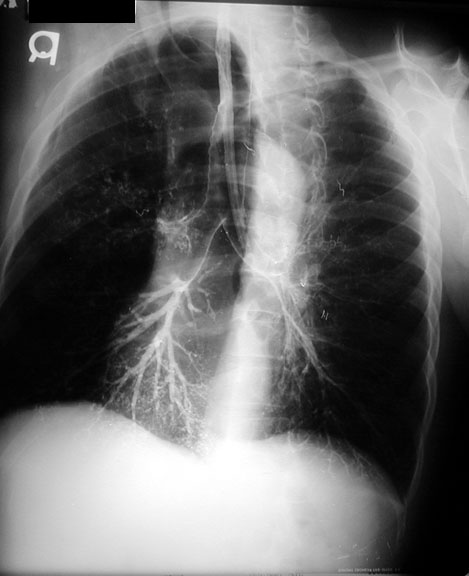

weekly clinical round for undergraduate from 8 to 11 AM during which interpretation of CHEST X rays was done for all cases of cardiothoracic surgery, gived by 2 staf member for 3 months